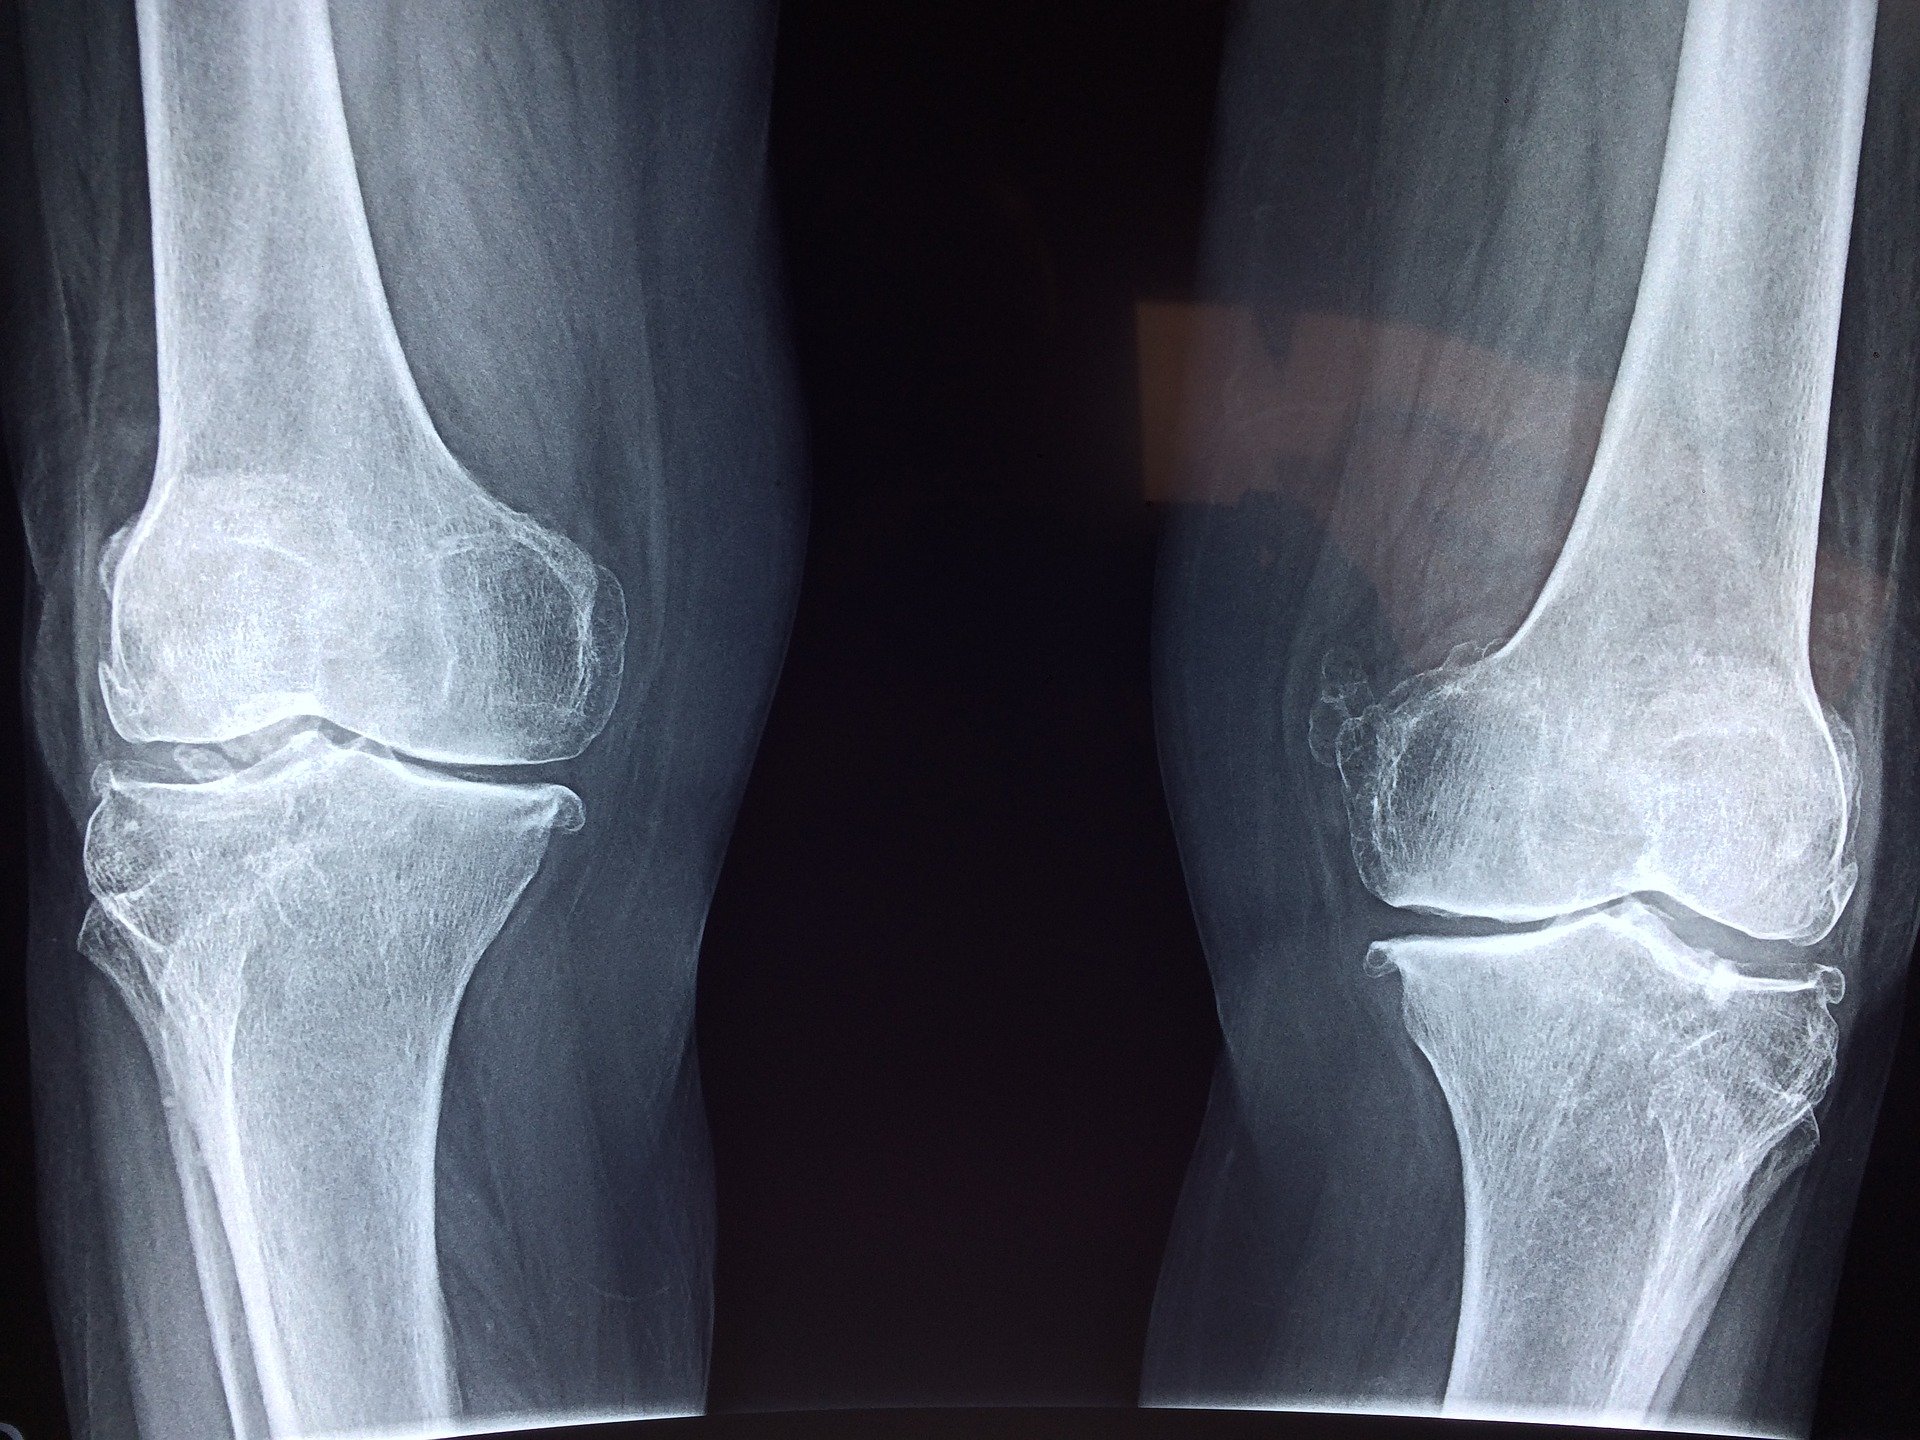

O to stara technika, którą sportowcy wykorzystali do zmniejszenia obrzęku i bólu kolan. Spuchnięte kolano może wskazywać na inne problemy zdrowotne. Jeśli problem nie ustępuje lub nasila się, najlepiej skonsultować się z lekarzem. Jeśli ból na początku jest łagodny i szukasz domowych sposobów na zmniejszenie obrzęku i bólu, możesz spróbować tych środków.